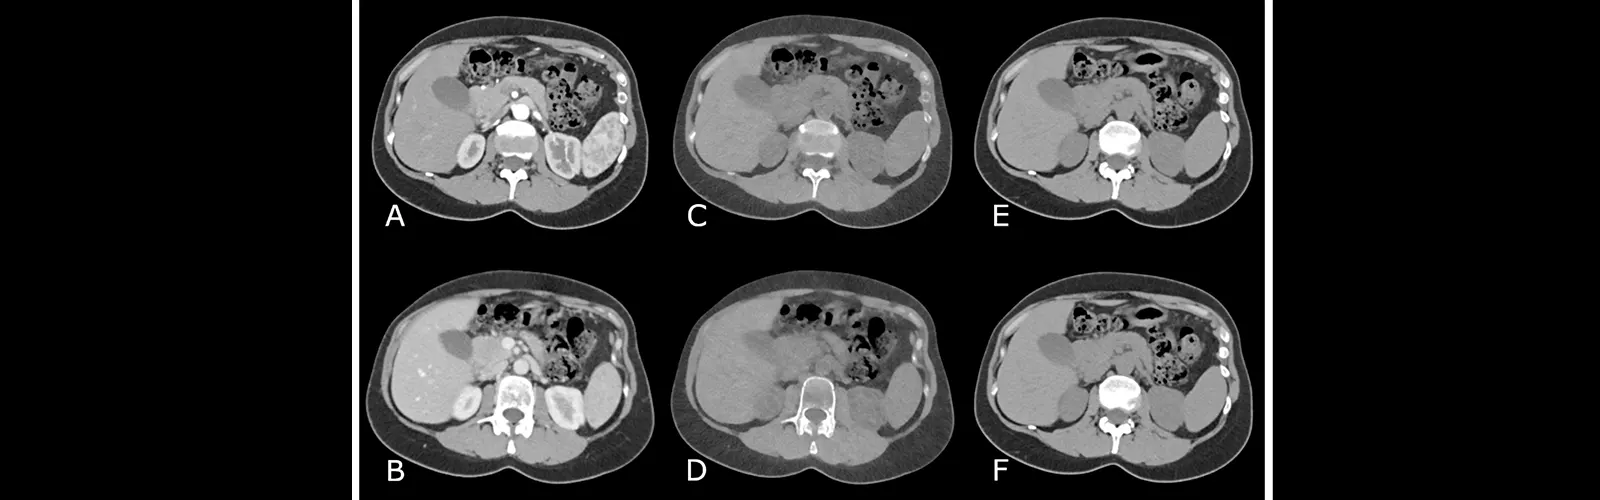

Non-contrast Computed Tomography (NCCT) of the Abdomen is what this term refers to. It is a form of diagnostic imaging procedure that produces in-depth images of the abdomen region using X-rays and computer technology.

Non-contrast Computed Tomography of the Abdomen is what this term refers to. It is a form of diagnostic imaging procedure that produces in-depth images of the abdomen region using X-rays and computer technology. The following are only a few advantages of NCCT Abdomen:

NCCT Abdomen offers extremely comprehensive views of the abdominal organs, including the liver, spleen, pancreas, kidneys, and colon, enabling medical professionals to spot even minute abnormalities that other imaging tests would miss.

Overall, NCCT Abdomen is a valuable diagnostic tool that provides accurate and detailed images of the abdominal region, which can help doctors, diagnose and manage a wide range of abdominal conditions effectively.